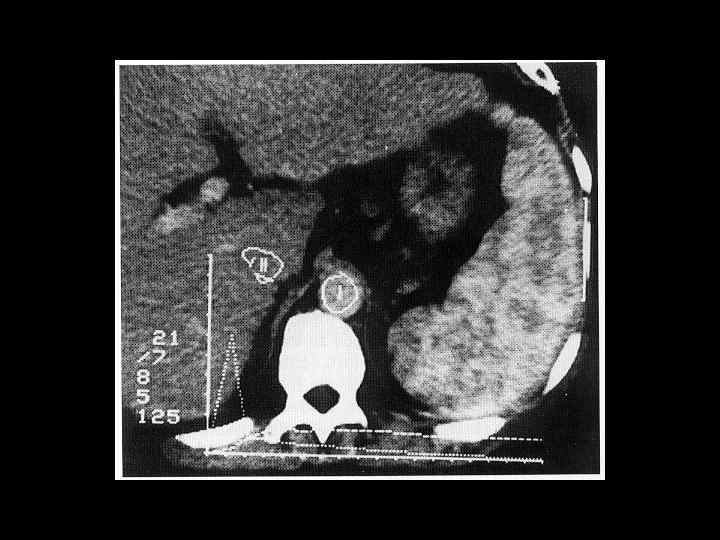

АКТУАЛЬНЫЕ ВОПРОСЫ РЕНТГЕНОЛОГИИ ЛУЧЕВАЯ ДИАГНОСТИКА ЗАБОЛЕВАНИЙ СЕЛЕЗЕНКИ Кисты и абсцессы селезенки

АКТУАЛЬНЫЕ ВОПРОСЫ РЕНТГЕНОЛОГИИ ЛУЧЕВАЯ ДИАГНОСТИКА ЗАБОЛЕВАНИЙ СЕЛЕЗЕНКИ Травма и инфаркт селезенки

АКТУАЛЬНЫЕ ВОПРОСЫ РЕНТГЕНОЛОГИИ ЛУЧЕВАЯ ДИАГНОСТИКА ЗАБОЛЕВАНИЙ СЕЛЕЗЕНКИ Опухолевое поражение селезенки